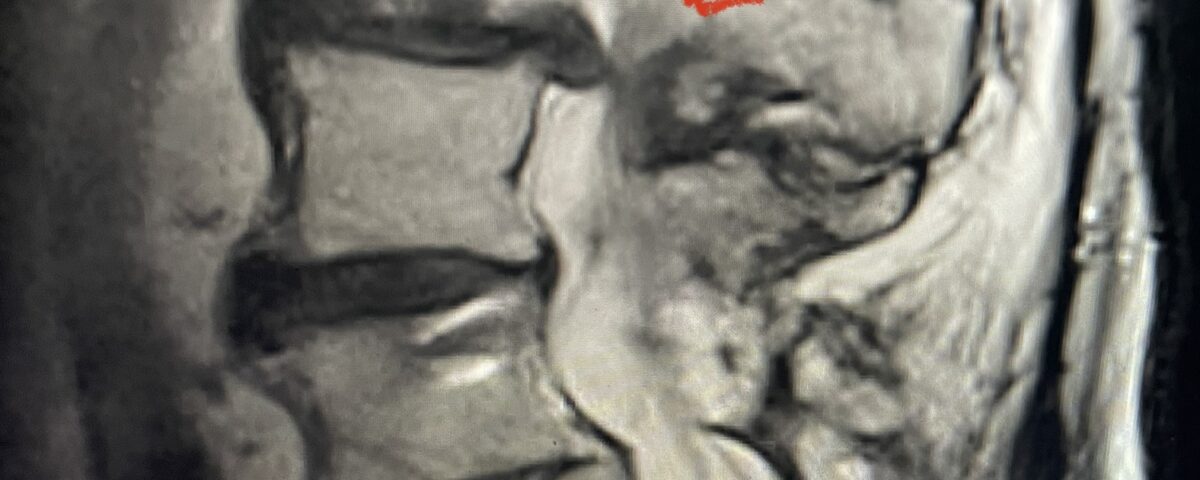

In patients who have lumbar spinal stenosis and significant cardio/pulmonary conditions, surgery is the last resort. However, some patients with these conditions may fail all means of conservative management where surgery becomes their only option for relief. In those patients, one should strive to do the least complex surgery that is necessary to get the job done for them. In this case study, we are confronted with a new problem in a 78 year-old male patient that was in poor medical condition who had had two prior lumbar laminectomies with resultant fusion and instrumentation from L4-S1. There was now retrolisthesis of L2-3 with severe stenosis (Fig.1)

Fig 1a: Sagittal T2 weighted lumbar MRI demonstrating severe L2-3 stenosis (red arrow)

Fig 1b: axial T2-weighted MRI demonstrating severe lumbar stenosis (red arrow)